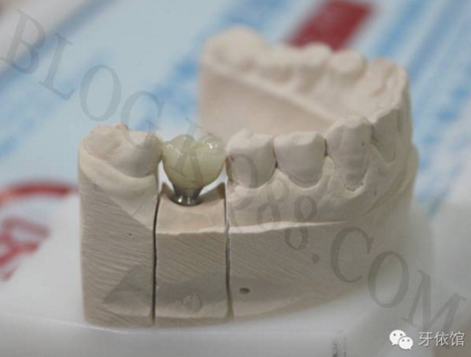

烤瓷牙制作完成。